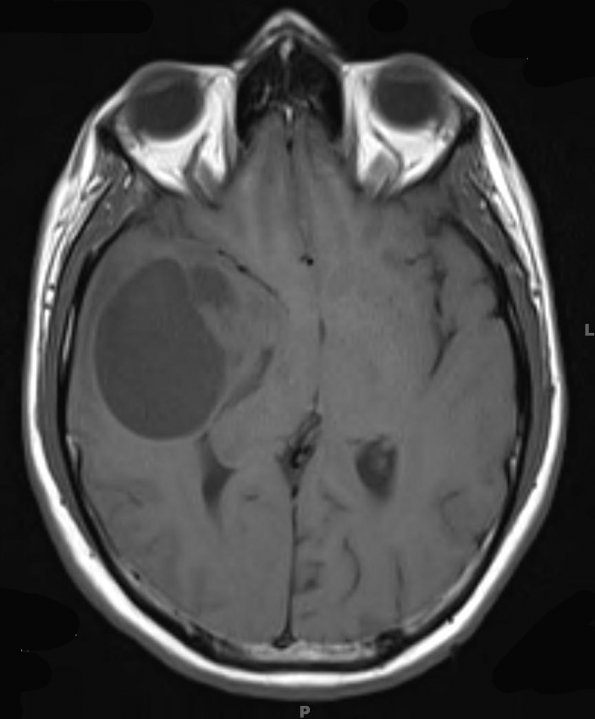

The patient is a 33 year old man with a right frontotemporal brain mass/cyst and headaches. Operative procedure: Biopsy

7A1-3 MRI scans show hypointensity in T1-weighted image with patchy rim enhancement with contrast (7A2).